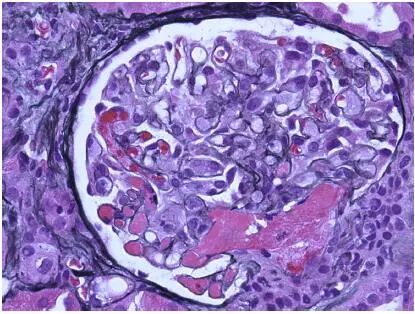

CNI肾毒性导致的血管收缩无形态学变化。急性CNI肾毒性特征包括:近端肾小管上皮细胞空泡化,大小一致;血管损伤,平滑肌细胞丢失;肌细胞胞浆空泡化;细胞坏死或凋亡退化。肌细胞损伤最终发展为局灶性结节性玻璃样变和透明样变,可延伸至小动脉和动脉血管壁整个中层。CNI肾毒性还可引起血栓性微血管病变(TMA),主要累及小动脉和肾小球毛细血管袢。慢性CNI毒性特征为:条状间质纤维化,肾小管萎缩。

近端肾小管上皮细胞空泡化,大小相等,内质网扩张,大型溶酶体。动脉中层和外膜透明质酸积聚。TMA患者可出现肾小球内皮细胞肿胀,内层扩张和肾小球系膜溶解。

图2 CNI肾毒性TMA,肾小球毛细血管袢和血管极(Jones 银染)